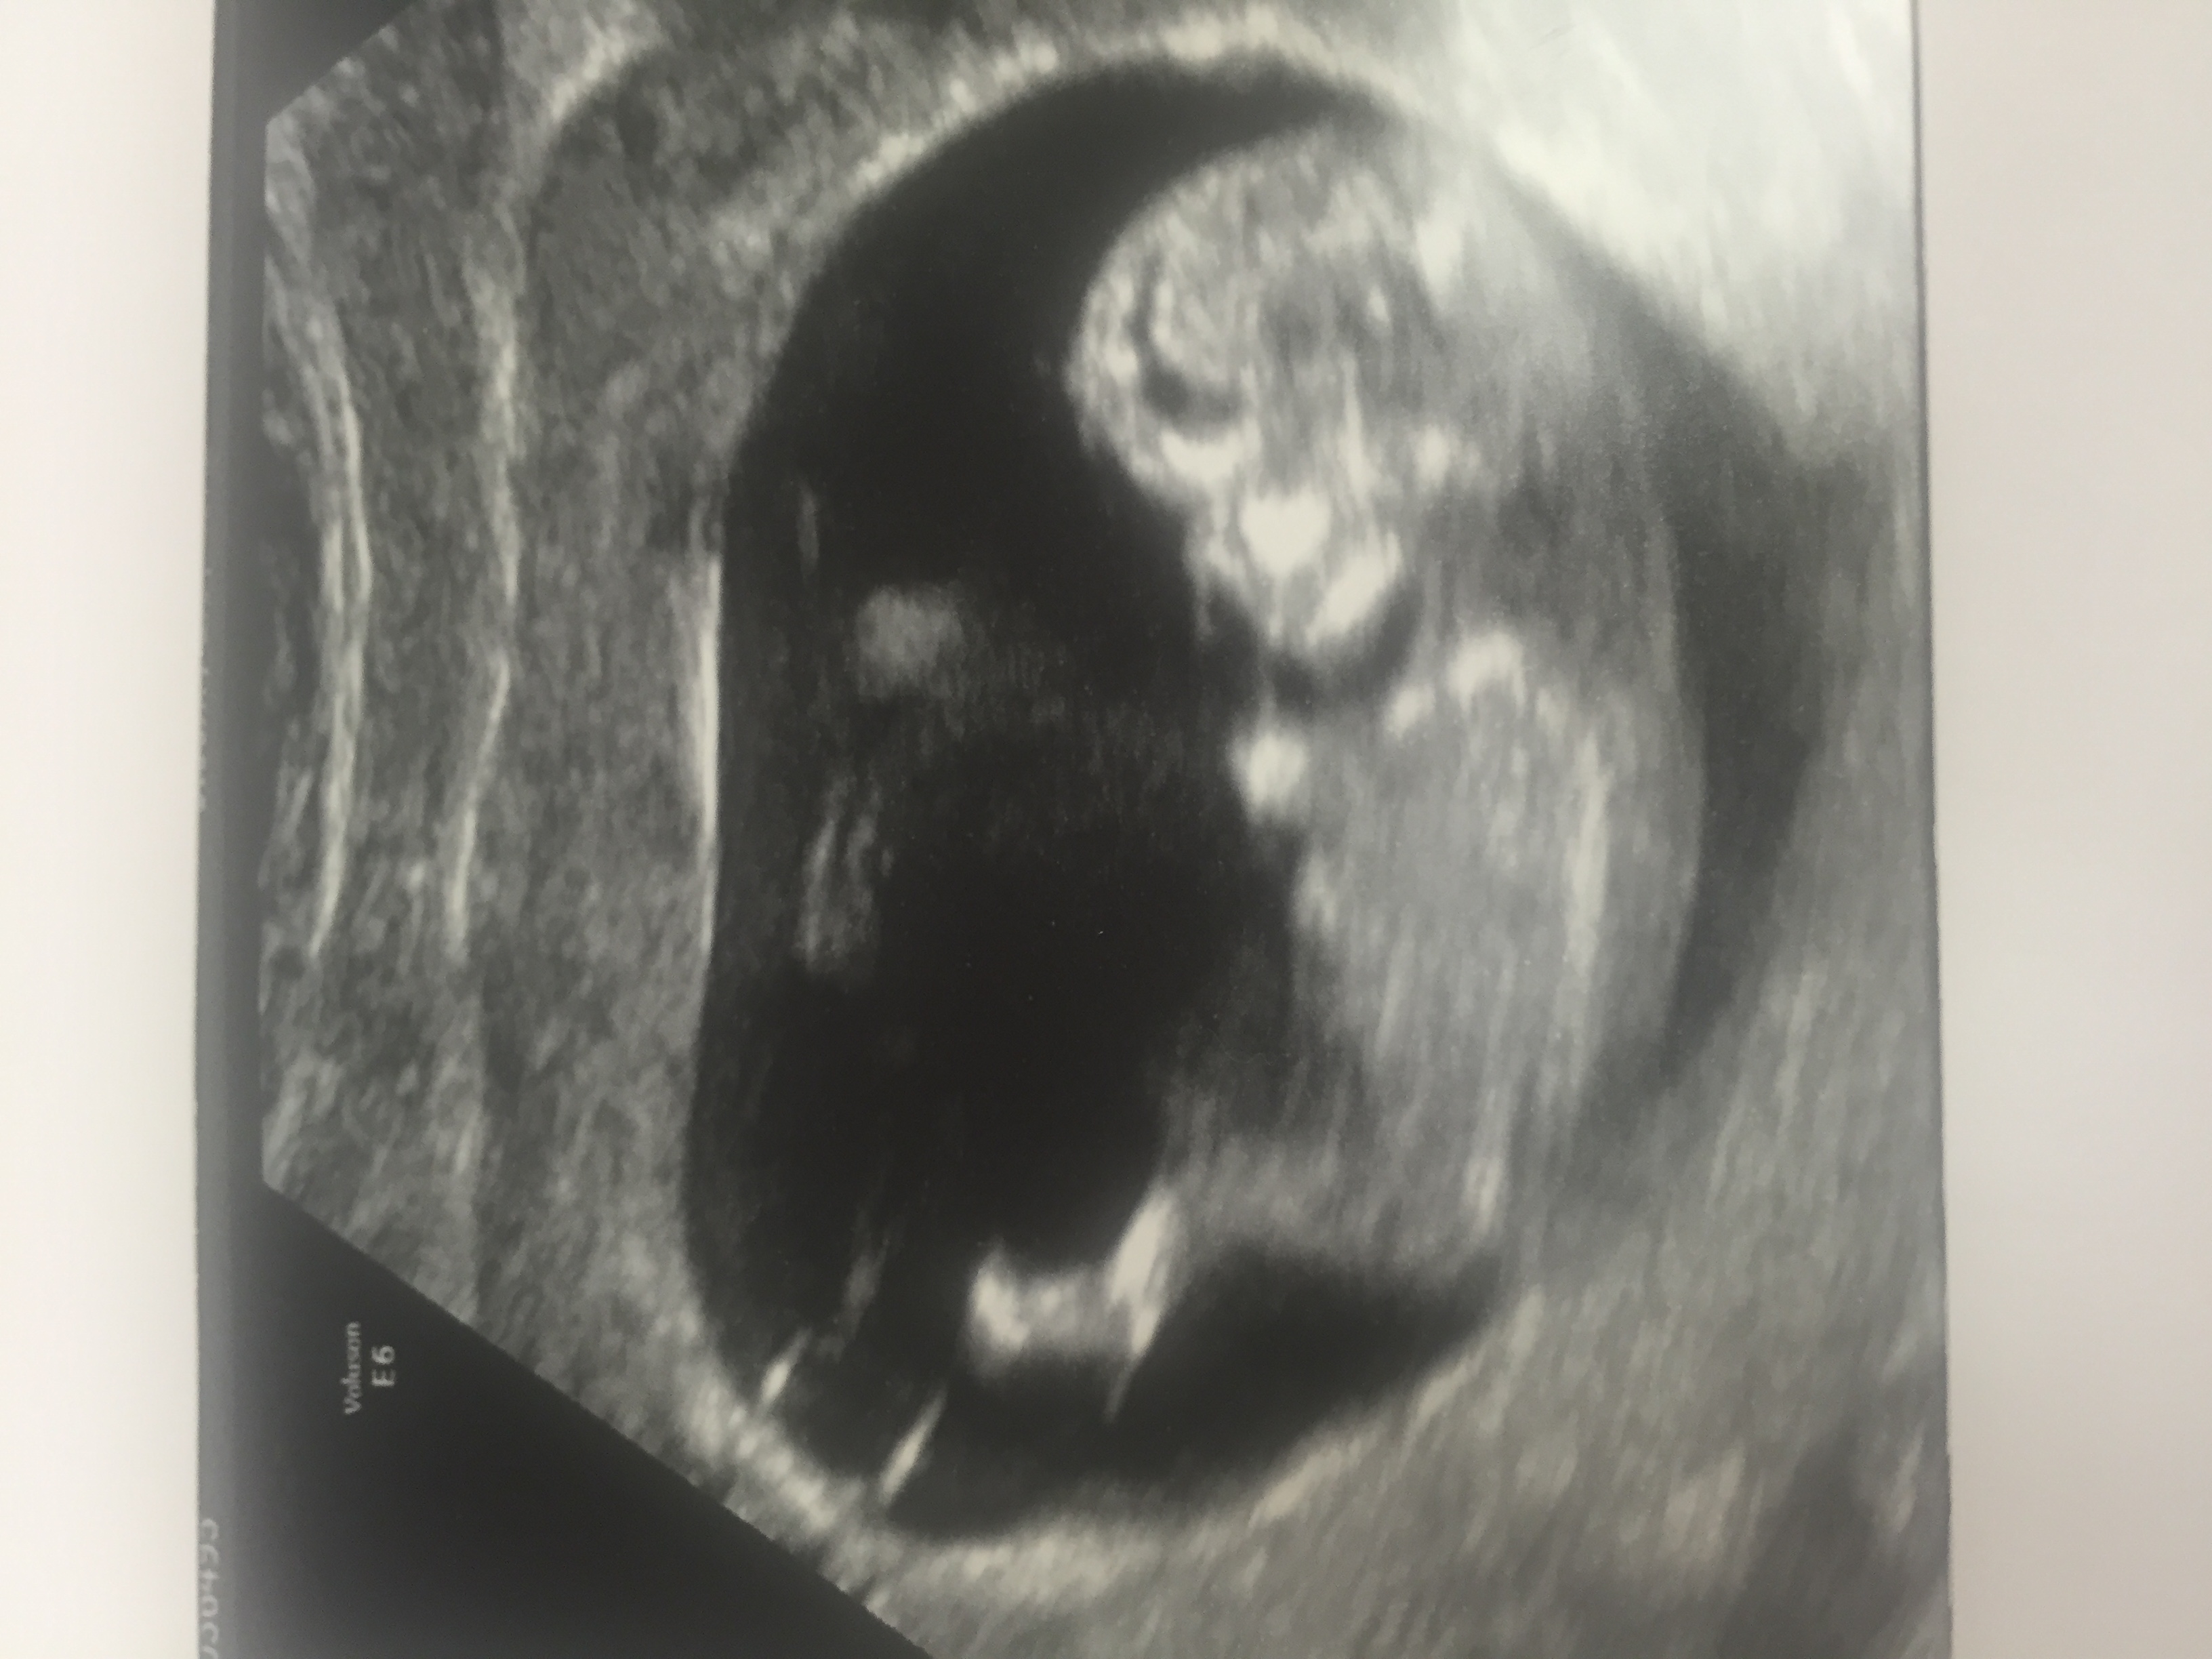

The nub looks slightly angled, but I think that it is parrallel to the bottom of the spine, since baby is on a slight angle.